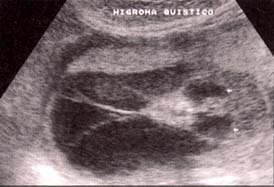

La forma letal del síndrome se presenta con higroma quístico ( Fig.4 ), edema generalizado, derrames pleurales , ascitis, anomalías cardíacas y riñón en herradura.

| Fig. 4. Onfalocele en un feto afecto de trisoma 13. | Fig. 5. Higroma quístico en un feto con síndrome de Turner. |